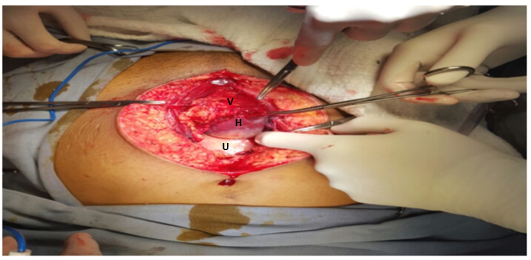

Al cuarto día postparto la paciente relata dolor en FII sin alteraciones en el transito urinario o digestivo. Al examen febril 38,5 ºC. Abdomen: blando, depresible, se palpa tumoración dolorosa en FII sin elementos de irritación peritoneal. El hemograma presenta glóbulos rojos 3.56mill/µL, hemoglobina de10.2 g/dL, hematocrito 31.9 %, 20.3mil/µL glóbulos blancos, plaquetas 384000/mL. Proteína C reactiva 91 mg/L.Función renal, hepática y crasis normales. Se solicita ecografía transvaginal que informa: Útero de 156 mm de longitud por 72 mm transverso y 85 mm antero posterior. En cara posterior izquierda una imagen heterogénea de 99 mm por 51mm, compatible con hematoma. Para valorar extensión del mismo se complementa con resonancia magnética (RM) abdomino pélvica que informa: útero aumentado de tamaño de 193 mm diámetro longitudinal sin imágenes patológicas en cavidad uterina. Colección en pelvis menor, a nivel de fosa ilíaca izquierda de 138mm longitud por 70 mm transverso por 68 mm antero posterior sin realce con contraste y en continuidad con ésta dos imágenes, una pararectal izquierda de 70mm de longitud por 33mm transverso y 66 mm anteroposterior, la otra en espacio pararectal derecho de 48mm de longitud por 28mm transverso y 70mm anteroposterior. (Figura I y II). En suma: hematomas subagudos subperitoneales en FII y a ambos lados del recto. Ante la evolución desfavorable y con planteo de hematoma del ligamento ancho complicado por proceso infeccioso se opta por laparotomía exploratoria y terapéutica. En el intraoperatorio se visualizan múltiples hematomas subperitoneales y en el ligamento ancho izquierdo que se evacúan, no sangrado activo, se realiza lavado del lecho y se coloca drenaje por contra abertura. (Figura III). La paciente se retira estable del block quirúrgico, se instaura nuevo plan antibiótico en base a Imipenem 500mg cada 6 hs i/v. Evoluciona favorablemente sin dolor ni síndrome toxoinfeccioso, no alteración en los tránsitos, genitorragia escasa. A los 30 días se otorga alta con tomografía computada de abdomen y pelvis que evidencia reducción de colecciones mayor al 50%. Seguimiento en primer nivel de atención clínico e imagenológico con alta a los 60 días posparto con resolución total de colecciones.